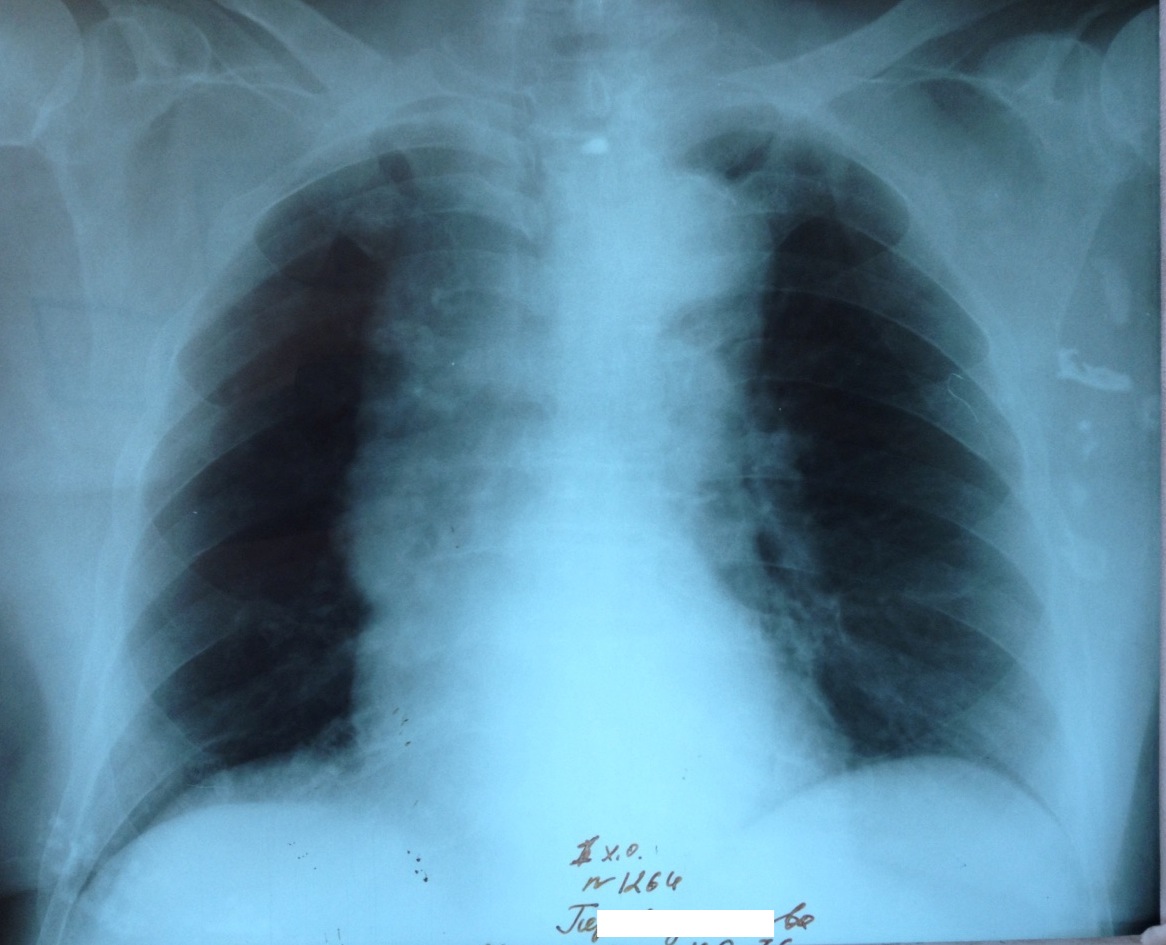

Расширение срединной тени. Рентген и результаты КТ.

IMG_4165-.jpg

IMG_4598-.jpg